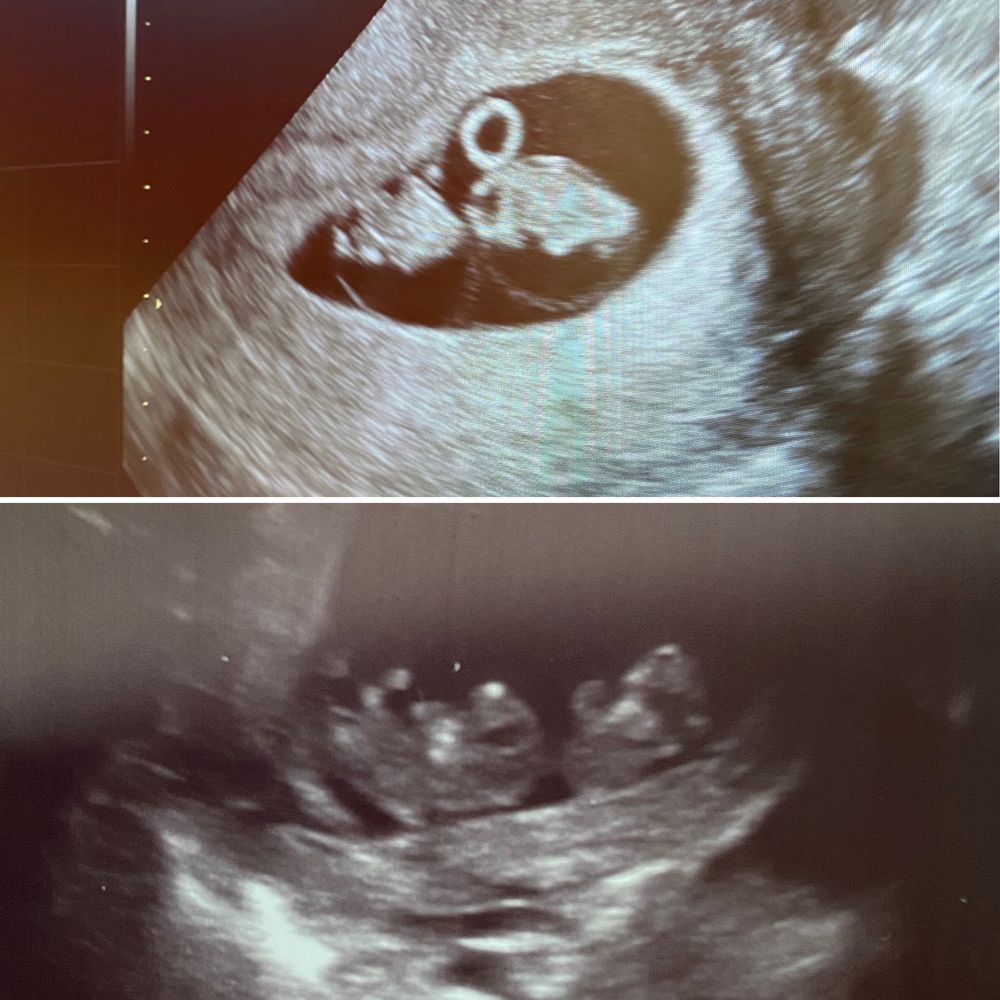

Двойня или один?)

Мне кажется тут явно видно двойняшек 😍

Близнецов подозревают? ПЯ ведь одно на фото. Вот мои близняшки, сверху 7.4, снизу 10.3 Изображение

Таня Орозова, да близнецы думала я тоже , вот у вас на 7+4 прям хорошо видно !! Моно моно у вас? Спасибо за фото !

Изображение Это в понедельник Изображение Это сегодня

Anna, в понедельник точно двое, сегодня вроде один, либо прячется) но я не поняла… почему она сначала говорит что бьются сердца, а потом меняет мнение и говорит что один?😕

Деметра, неее в понедельник видно же что двойня, у меня так же отображаются малыши по узи, а вот сегодня да, не понятно, но я думаю что один явно прячется☺️, решил с мамой в прятки поиграть☺️пусть будет так, дай Бог🙏🏼🙏🏼🙏🏼